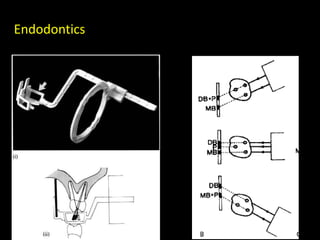

3. Special considerations for intra-oral radiography include techniques for mandibular third molars, gagging patients, endodontic procedures, edentulous ridges, and pediatric patients.